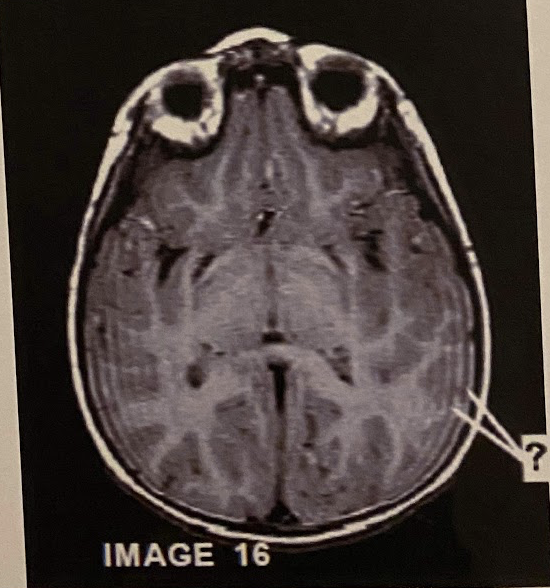

Q

The artefact demonstrated on the multi-slice/multi-angle sagittal oblique T2 FSE in this image is due to:

a) coil failure

b) Interslice cross excitation

A